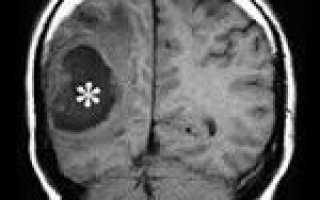

Точность диагностирования абсцесса головного мозга с помощью КТ головного мозга зависит от стадии формирования абсцесса. На ранних стадиях заболевания диагностика затруднена. На этапе раннего энцефалита (1-3 сутки) КТ определяет зону сниженной плотности неправильной формы. Введенное контрастное вещество накапливается неравномерно, преимущественно периферических отделах очага, реже в центре. На более поздних этапах энцефалита контуры очага приобретают ровные округлые очертания. Контрастное вещество распределяется равномерно, по всей периферии очага; плотность центральной зоны очага при этом не меняется. Однако на повторной КТ (через 30-40 минут) определяется диффузия контраста в центр капсулы, а также наличие его и в периферической зоне, что не характерно для злокачественных новообразований.

Инкапсулированный абсцесс мозга на КТ имеет вид округлого объемного образования с четкими ровными контурами повышенной плотности (фиброзная капсула). В центре капсулы зона пониженной плотности (гной), по периферии видна зона отека. Введенное контрастное вещество накапливается в виде кольца (по контуру фиброзной капсулы) с небольшой прилежащей зоной глиоза. На повторной КТ (через 30-40 минут) контрастное вещество не определяется.

МРТ головного мозга — более точный метод диагностирования абсцесса головного мозга. При проведении МРТ на первых стадиях формирования абсцесса мозга (1-9 сутки) энцефалитический очаг выглядит: на Т1-взвешенных изображениях — гипоинтенсивным, на Т2-взвешенных изображениях — гиперинтенсивным. МРТ на поздней (капсулированной) стадии абсцесса головного мозга: на Т1-взвешенных изображениях абсцесс выглядит, как зона пониженного сигнала в центре и на периферии (в зоне отека), а по контуру капсулы сигнал гиперинтенсивный. На Т2-взвешенных изображениях центр абсцесса изо- или гипоинтенсивный, в периферической зоне (зоне отека) гиперинтенсивный. Контур капсулы четко очерчен.